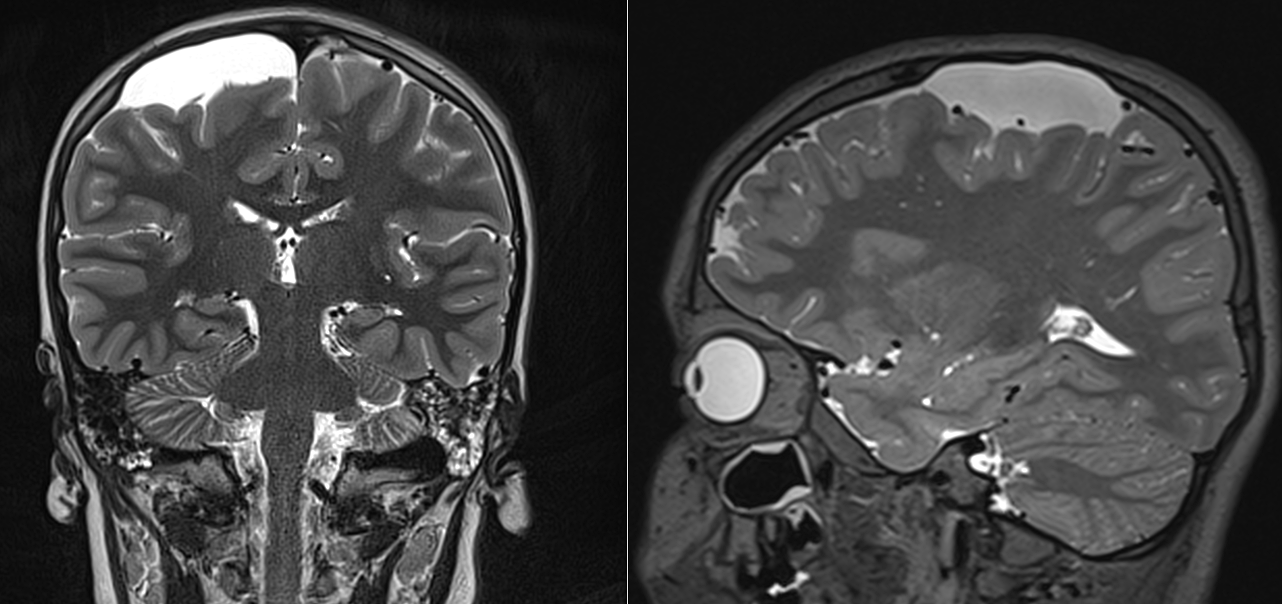

Imagistica este esențială pentru identificarea chistelor arahnoidiene:

- RMN (rezonanță magnetică nucleară): metoda preferată, evidențiază conținutul de LCR și raporturile cu structurile cerebrale.

Chistul arahnoidian apare ca o leziune hipointensă pe imaginile T1 și hiperintensă pe imaginile T2, cu semnal identic cu cel al lichidului cefalorahidian.